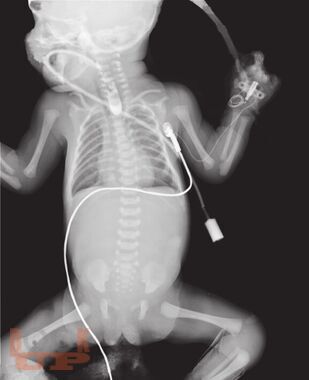

В методическом пособии описаны наиболее распространенные аномалии и пороки развития пищеварительного тракта у детей, а также лучевые методы исследования, с помощью которых диагностируют такие аномалии и пороки.

Пособие иллюстрировано фотографиями оригинальных рентгенограмм и схемами, облегчающими понимание изложенной темы.